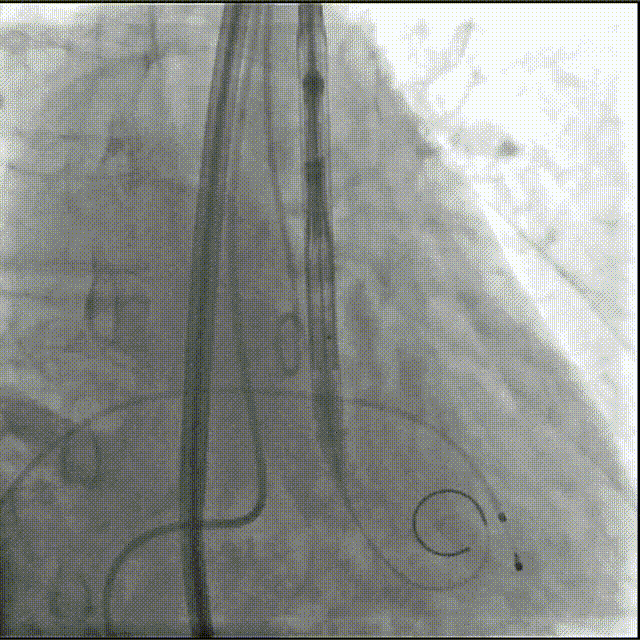

瓣膜0位定位释放

瓣膜稳定释放至全展开,无明显下滑,位置稳定

造影评估,瓣膜位于瓣下2mm形态稳定

左冠切线评估,小弯侧深度6mm

无张力脱钩,瓣膜无位移

最终造影,无瓣周漏